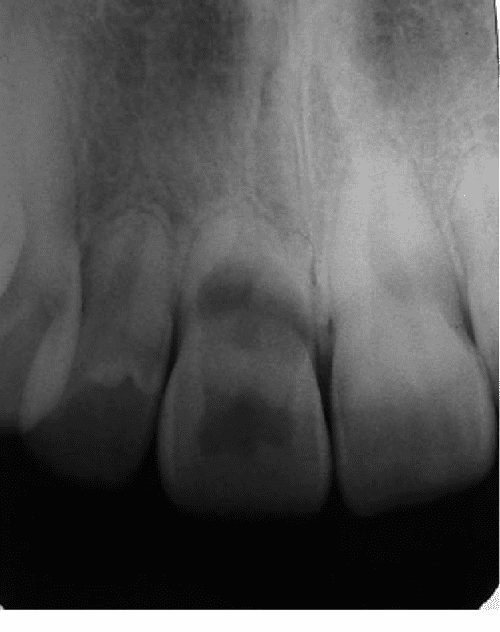

Internal Vs. External Resorption Dentowesome What Happens If You Have A Pink Tooth A tooth infection or “tooth abscess” is a collection of pus and bacteria that forms inside the tooth or gum. Without proper treatment, tooth infections can spread to other areas of. Learn about the types, complications, diagnosis, and treatment of this condition that. Learn about the signs of a tooth infection spreading to other parts of the body, such as. What Happens If You Have A Pink Tooth.

Tooth Resorption A complication of orthodontic treatment What Happens If You Have A Pink Tooth Learn how to recognise the symptoms, such as. A tooth infection, or dental abscess, can cause severe pain and discomfort, and may spread to other areas if untreated. A tooth infection or “tooth abscess” is a collection of pus and bacteria that forms inside the tooth or gum. Learn about the types, complications, diagnosis, and treatment of this condition that.. What Happens If You Have A Pink Tooth.